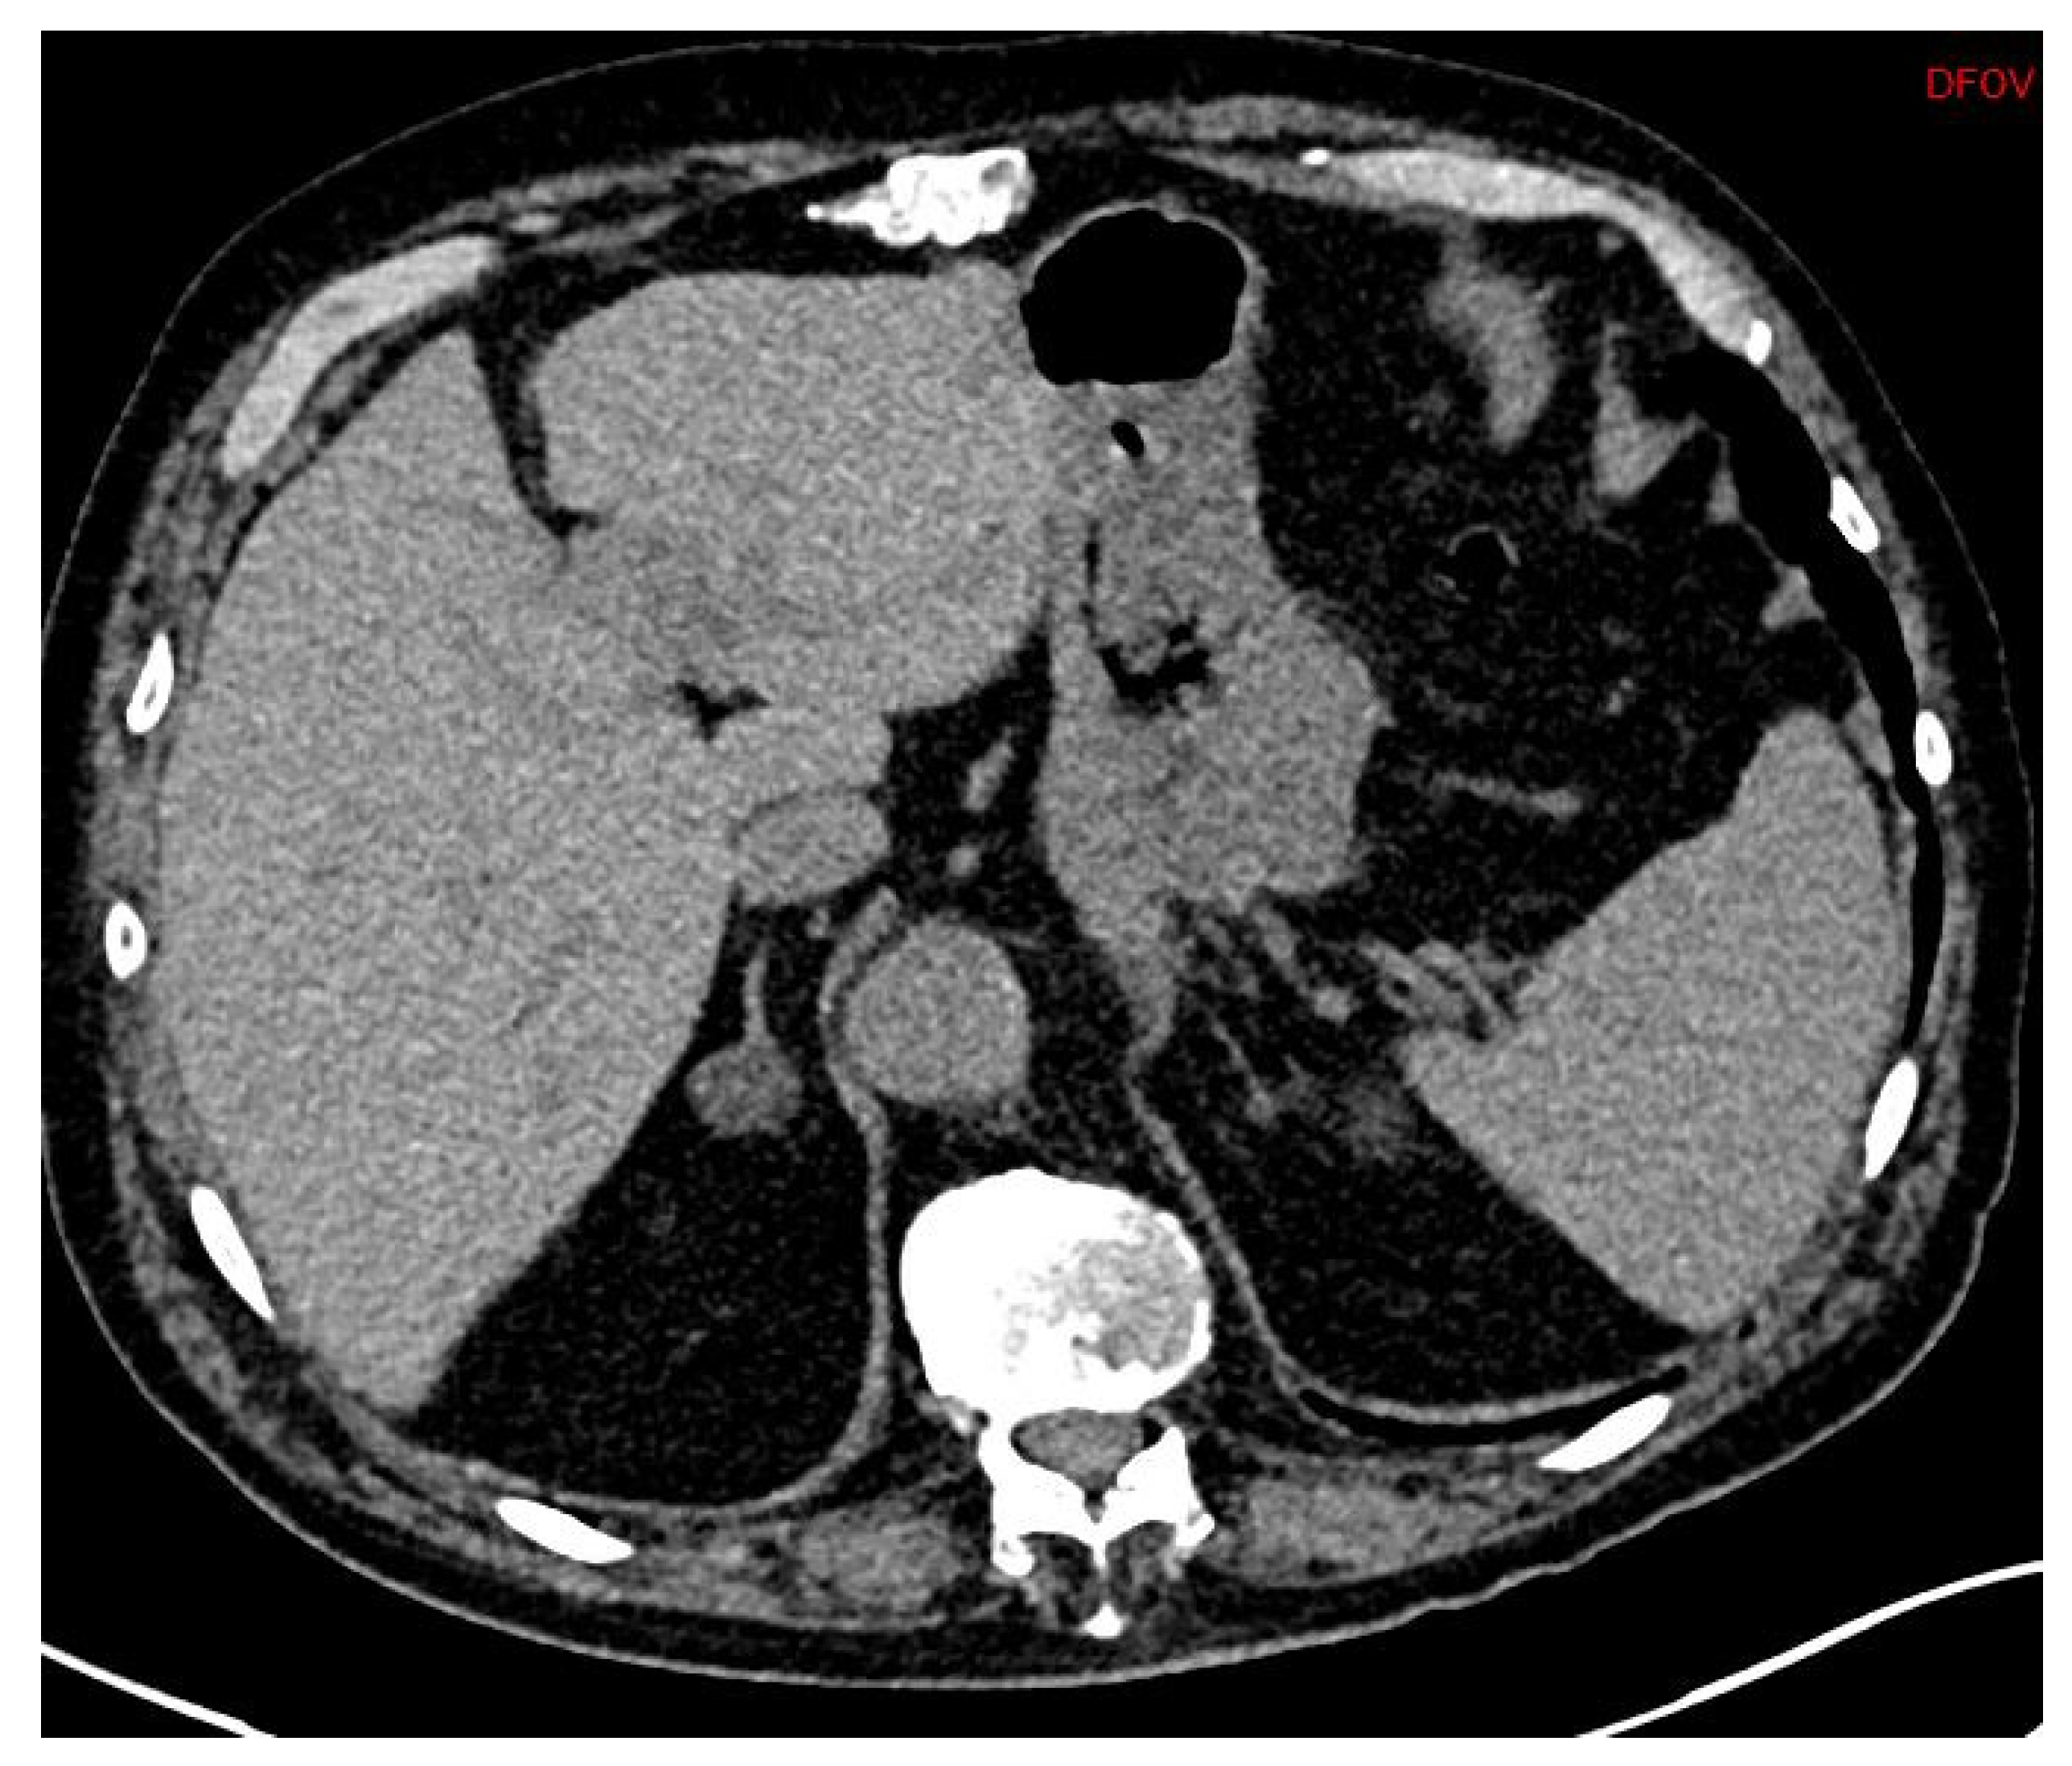

First, adrenal imaging is required, and the preferred method is computed tomography (CT) scanning with contrast, because the spatial resolution is better than magnetic resonance imaging (MRI)’s. CT scanning detects adrenal adenomas (Figure 1) but provides no information about aldosterone secretion and, therefore, cannot distinguish between aldosterone-producing adenomas (APA) and non-secretory adrenal adenomas. Moreover, micro-APAs are frequent in patients with confirmed PA and can be missed by adrenal imaging. It is, however, useful to exclude malignant adrenal tumors such as carcinoma, which might in rare cases produce aldosterone [24].

APAs are classically unilateral adrenal tumors from 10 to 20 mm, with a density of less than 10 UH. However, unilateral forms of PA can also occur as unilateral hyperplasia or even normal adrenal glands. A study of 950 patients showed that imaging techniques (CT or MR) were discordant compared with adrenal vein sampling (AVS) in 38% of cases (15% of cases were classified as unilateral instead of bilateral, 19% of cases were incorrectly classified as bilateral when they were unilateral, and even 4% of cases were classified as unilateral but on the wrong side) [25].

In conclusion, imaging alone is not sufficient to diagnose PA subtypes.

Figure 2. Abdominal CT (DFOV 85 × 37 mm): Pheochromocytoma, left heterogenous adrenal tumor.